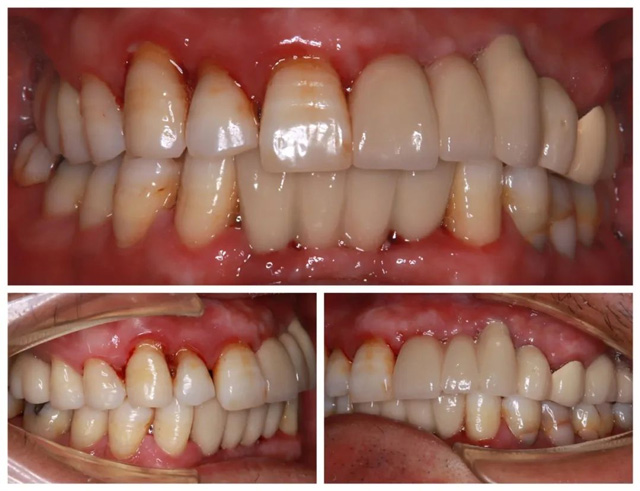

經CBCT全景檢查所見,謝海洋主任發現卞先生存在多顆牙缺失、殘存牙體伴有嚴重骨吸收,且多顆修復體失效等問題,亟待通過種植牙重建咬合功能。針對顧客異地就醫、就診時間有限的情況,謝海洋主任為卞先生制定了“上下頜多顆即拔即種+連冠修復”的個性化種植方案:下頜種植2顆基牙支撐2顆連冠,上頜右側種植2顆獨立基牙,上頜前側種植3顆基牙連冠修復1顆。

為確保治療的質量與效率,醫院特別開通綠色通道,協調種植體供應商優先供貨,各科室無縫銜接診療環節。術后卞先生順利佩戴隱形義齒過渡,考慮到其工作休假的特殊性,醫院根據卞先生的安排,貼心將正式牙冠安裝時間延至2025年1月。

“原本擔心異地就診麻煩,沒想到每個環節都安排得井井有條。從接診到治療全程高效專業,這種真正為患者著想的服務太難得了!”卞先生表示,“從1月份佩戴完正式牙冠到現在,我是吃嘛嘛香!”